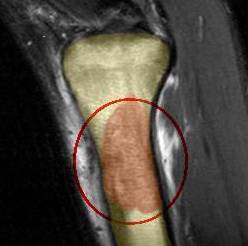

- Компьютерная и магнитно-резонансная томография. Данные методы исследования заключаются в проведении цифровой обработки результатов рентгенографии. Врач-онколог на томографическом снимке может определить локализацию, размер и форму ракового очага костной ткани.